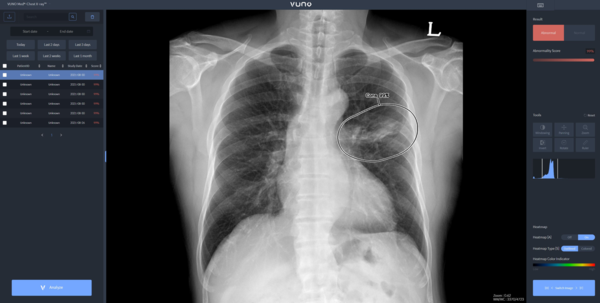

뷰노메드 체스트 엑스레이는 흉부 엑스레이 영상에서 결절, 경화, 간질성 음영, 흉수, 기흉 등 주요 이상 소견을 높은 정확도로 탐지하는 인공지능 솔루션이다. 의료진에게 이상 소견의 소견명과 위치를 제시해 결핵, 폐렴 등 주요 폐 질환 진단을 돕는다. 경량화된 모델로 개발돼 다양한 엑스레이 장비에 쉽게 연동할 수 있는 것이 특징이다.